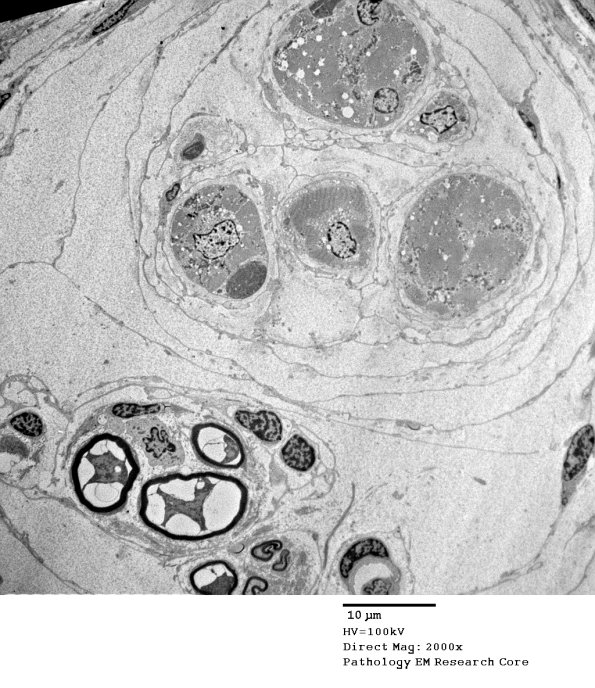

A muscle spindle and its innervating nerve are shown in this electron micrograph.